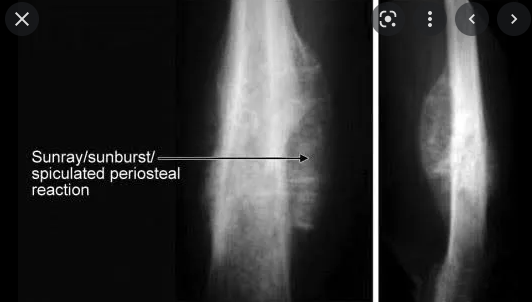

What are sunray spicules?

calcification within the tumour but outside the bone

How can you spot osteosarcoma on an X-ray?

A

1. ill-defined lesion with an indistinct zone of transition

2. sclerotic or lytic areas within the lesion

3. cortical destruction

4. codman triangle

5. sunray spicules